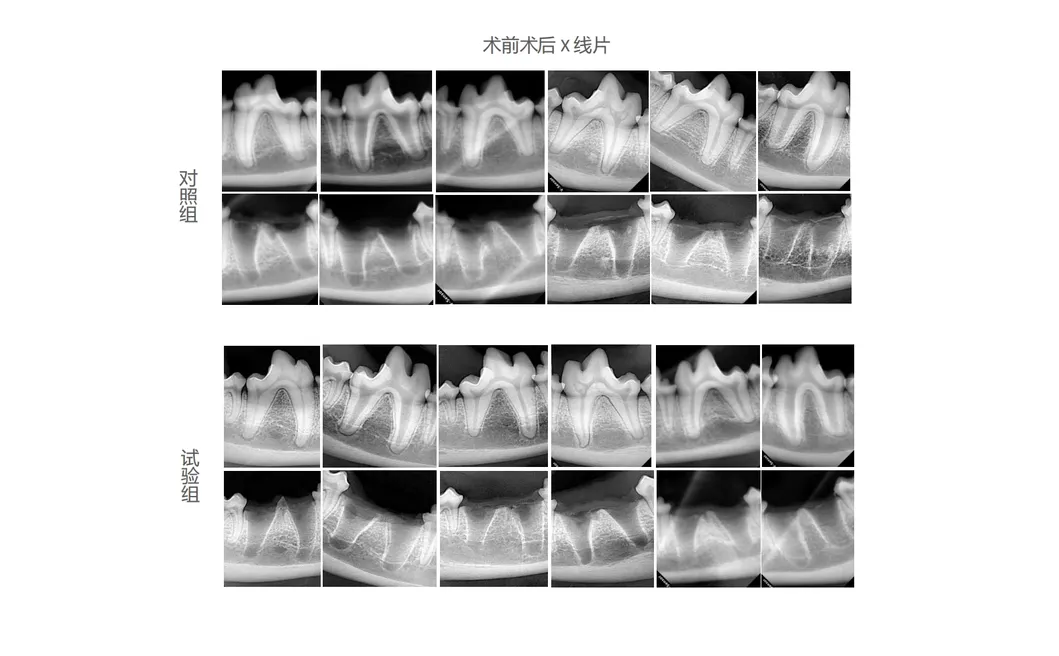

In this groundbreaking scientific study, dogs were handpicked as the ideal experimental subjects to evaluate the unparalleled effectiveness of our innovative dental tools. The control group continued to use traditional manual tooth extraction devices, while the treatment group was introduced to the revolutionary Golden Cudgel-Pneumatic Dental Elevator Kit. Researchers conducted meticulous observations, sparing no detail in documenting crucial factors such as physiological parameters, frequency of intraoperative complications, extraction duration, and the degree of damage to the extraction socket. The study thoroughly assessed postoperative soft tissue healing, scrutinized haematological data, and carried out comprehensive imaging and histological evaluations. The extensive data harvested from these observations were subjected to rigorous statistical analysis, unveiling valuable insights that highlighted the superior performance of our advanced dental tools.